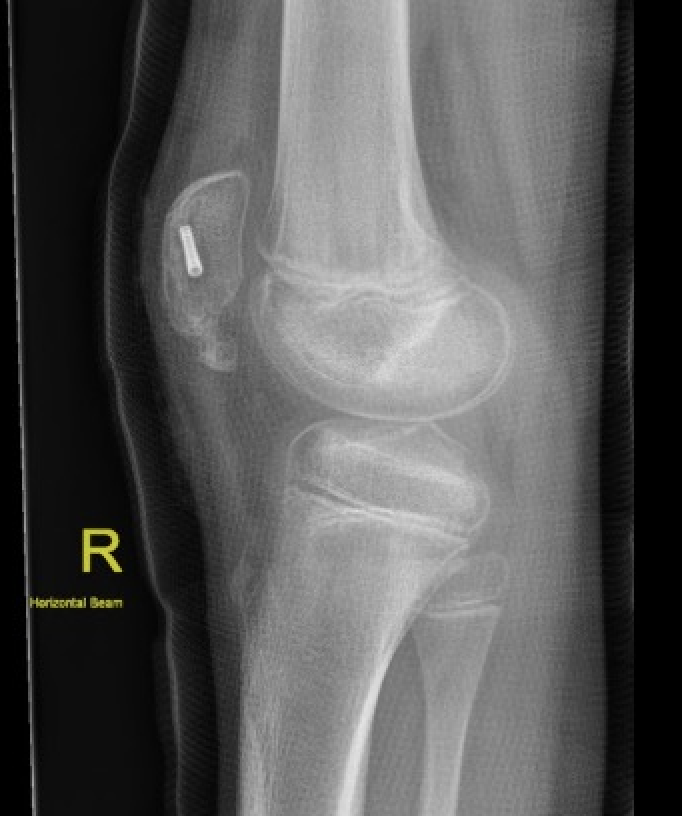

Xray

Patella alta / high riding patella

Very small bony fragment

Minimally displaced patella sleeve fracture